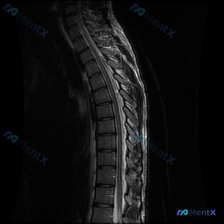

这是一份胸椎MRI T2序列矢状位影像,扫描范围覆盖胸椎主要节段,图像质量好无明显伪影。

- 整体结构:胸椎保持正常生理性后凸,无明显侧弯、椎体滑脱,序列完整

- 椎体与椎间盘:各椎体高度正常,骨髓信号均匀无异常;多个椎间盘存在T2信号降低,提示退行性改变,但未见明显椎间盘突出物突破后纵韧带突入椎管

- 关键异常发现:胸椎中上段(约T4-T7水平)可见后方韧带(黄韧带为主)明显肥厚、皱缩,呈弧形向椎管内突出,导致该水平椎管前后径明显变窄,硬膜囊后方受压,脊髓受压变形

- 脊髓状态:虽然脊髓受压变形,但T2序列上脊髓内未见明显异常高信号,暂无明确脊髓水肿或软化灶的影像学表现